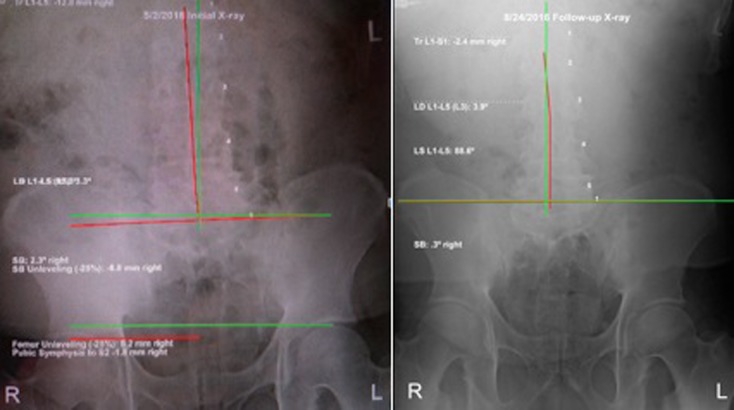

Posture analysis (Figure 1) as outlined by Harrison [6] revealed a forward head position, a prominent right head translation, a forward translated thorax, a right translated thorax, and a right laterally tilted pelvis.

The lateral full-spine radiograph (Figure 2) demonstrated a significant forward lean, as the measurement from the horizontal distance from the posterior-superior vertebral body corner of T1 to the posterior inferior body corner of S1 measured 192.3 mm (ideal=0 mm. [10] The lateral cervical specific image (Figure 3) demonstrated a forward head position of 67.5 mm (normal=0–15 mm [11]), an ARA from C2–C7 of –29.6° (normal= –31° to 42° [11–13]), and an atlas plane angle of –7.6° (normal= –29° [11, 12]). The AP cervico-thoracic view (Figure 4) showed a large right head translation (62.7 mm; normal=0 mm [10]), with a cervico-dorsal angle of –4.8° (normal=0° [10]) and an Rz angle of 15.6° (normal=0° [10]). The AP lumbar view (Figure 5) showed a right thoracic translation (–12.6 mm; normal=0 mm [10]), with unleveling of the pelvis lower on the right.

The patient’s posture as seen visually (Figure 1) improved dramatically. Follow-up radiographic assessment confirmed and quantified the significant improvements in the patient’s posture (Figures. 3–6).

The total body forward shift from T1-S1 reduced (132 mm vs. 192 mm),

forward head posture reduced (36.5 mm vs. 67.5mm),

there was an increased cervical lordosis (–37.2° vs. –29.6°),

an increased atlas plane angle (–19.8° vs. –7.6°),

a reduced lateral head translation (–46 mm vs. –62.7 mm) and

a reduced lateral thoracic translation (–2.4 mm vs. –12.8 mm).

The pelvis was also leveled out by the prescription of a 12 mm heel lift for the right leg.